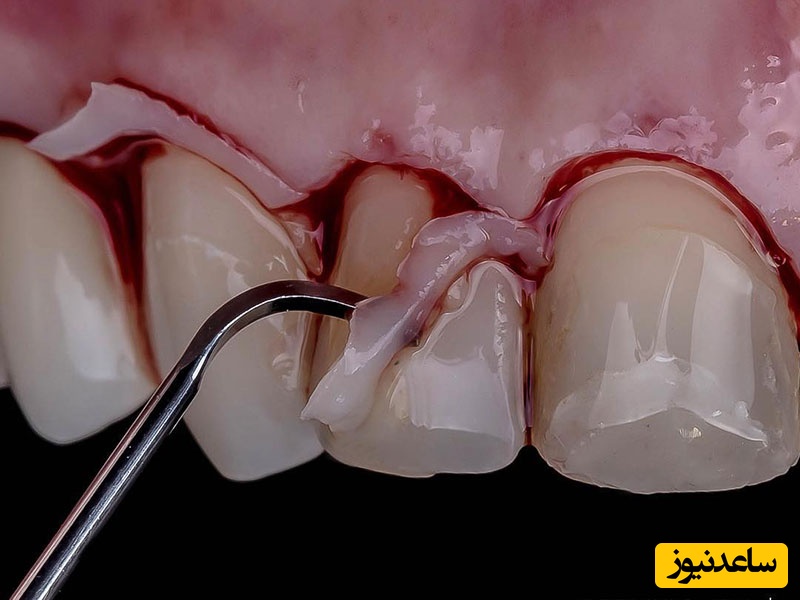

در این فرایند، جراح لثه ها را به سمت بیرون بر می گرداند و باکتری هایی که عامل بیماری شده اند را خارج می کند. سپس استخوان های پیوندی، غشا یا پروتئین های بافت لثه (یا ترکیبی از این سه مورد) را به لثه اضافه می کند تا بافت آن دوباره تشکیل شود و محکم به دندان بچسبد.

جراحی لثه تحلیل رفته (جراحی پیوند لثه)

در این روش، پریودانتیست بخشی از قسمت های دیگر بافت دهان را برمی دارد و به لثه ها پیوند می زند. این جراحی زمانی انجام می شود که لثه به دلیل بیماری از بین رفته یا اینکه مقداری از بافت آن تحلیل رفته باشد.